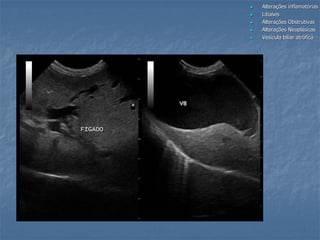

 Alterações inflamatórias Colangiohepatite,

Colecistite, Mucocele

 Litíases

 Alterações Obstrutivas

 Alterações Neoplásicas

 Vesícula biliar atrófica

Alterações da vesícula biliar

 Alterações inflamatórias